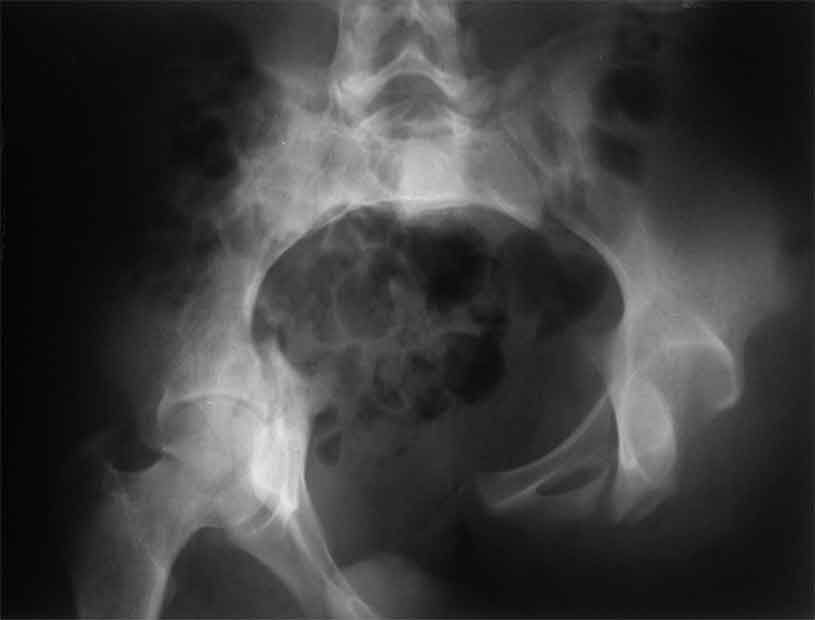

Уважаемые коллеги, сложный случай, интересует ваше мнение. Травма 2 месяца назад, в результате ДТП. При поступлении в лечебное учреждение по м/ж выполнено формирование культи на уровне в/3 левого бедра по (травматический дефект левой н/конечности), в послеоперационном периоде раневая инфекция, остеомиелит - экзартикуляция.

Повреждение таза лечилось консервативно. Интересует ваше мнение по поводу тактики лечения, попытаться свести аппаратом, а потом открытый этап (каким доступом/доступами)? другие варианты? С уважением Максим Агалаков

продолжение темы. не увидел энтузиазма в обсуждении. Вопросы прежние, первым этапом закрыто устранили вертикальное и передне-заднее смещение. Каким образом восстановить целостность тазового кольца, из каких доступов? Снимки в приложении

передне-неружным внебрюшинным доступом к лонно-седалищномц сочленению - синтез штангами(можно из заднего доступа, но хуже обзор и труднее репозиция), из этого же доступа к крыше вертлужной впадины - синтез реконструктивными пластинами(мы делали "ChM" тазовыми, хорошо себя зарекомендовали), передним доступом на лонное сочленение - синтез подобной пластиной. к задней колонне вертлужной впадины - задне-наружный доступ, синтез такой же пластиной. КРОВОПОТЕРЯ!!! возможно до 7л. мощная ангтибак. профилактика во время и после операции. до перехода на заднюю колонну оперировать в аппарате. бвл подобный случай, по снятии аппарата через 8 мес. - рецедив смещений сразу.